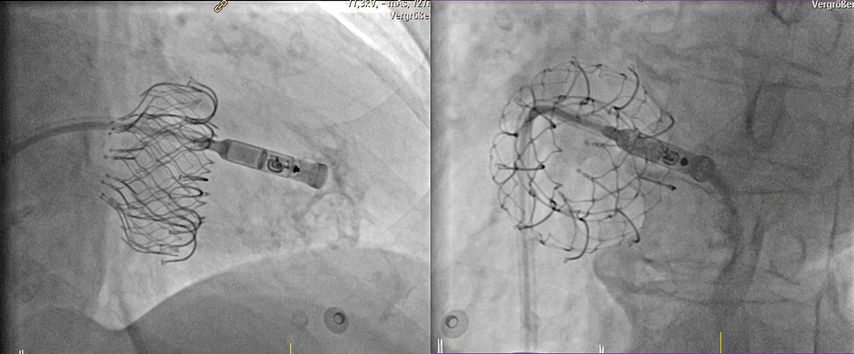

Bei bradykarden Herzrhythmusstörungen gibt es seit 2013 die Möglichkeit, einen sondenlosen Herzschrittmacher mittels Katheterverfahren in den rechten Ventrikel zu implantieren.10,11 Dies kann über die Femoralvene oder über die Jugularvene erfolgen. So können Patient:innen mit bradykardem Vorhofflimmern, aber auch bei z.B. seltenen Reflexsynkopen aufgrund von langen Pausen zwischen den Herzschlägen im VVI-Modus (VVI = ventrikulär, ventrikulär, inhibiert), sowie Betroffene mit höhergradigen AV-Blockierungen im VDD-Modus (VDD = Ventricular-DrivenDual-Chamber) des Herzschrittmachers, interventionell behandelt werden – allerdings mit nur bedingter atrioventrikulärer Synchronität. Der große Vorteil der sondenlosen Herzschrittmachertherapie ist die Tatsache, dass auch Patient:innen mit fehlendem venösem Zugang der oberen Körperhälfte oder bei deutlich erhöhtem Infektionsrisiko (z.B. vorangegangene Schrittmachersysteminfektion, chronische Hämodialyse) einer Schrittmachertherapie zugeführt werden können (Klasse-IIa-Indikation laut aktuellen ESC-Leitlinien).12 Außerdem sind sondenlose Systeme zu favorisieren, wenn ein Zustand nach Trikuspidalklappenersatz besteht (Abb. 4).

Abb. 4: Implantation eines sondenlosen Herzschrittmachers (Medtronic MicraTM) in den rechten Ventrikel bei vorbestehendem interventionellem Trikuspidalklappenersatz (EvoqueTM). Zur optimalen Positionierung wird über den Delivery-Katheter Kontrastmittel verabreicht. Die sondenlose Schrittmacherkapsel ist noch mit dem Delivery-Katheter verbunden. Links: Ansicht von schräg rechts vorne (RAO), rechts: Ansicht von schräg links vorne (LAO)